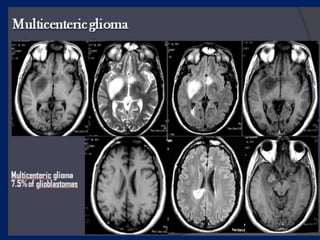

Multicenteric glioma

7.5% of glioblastomas